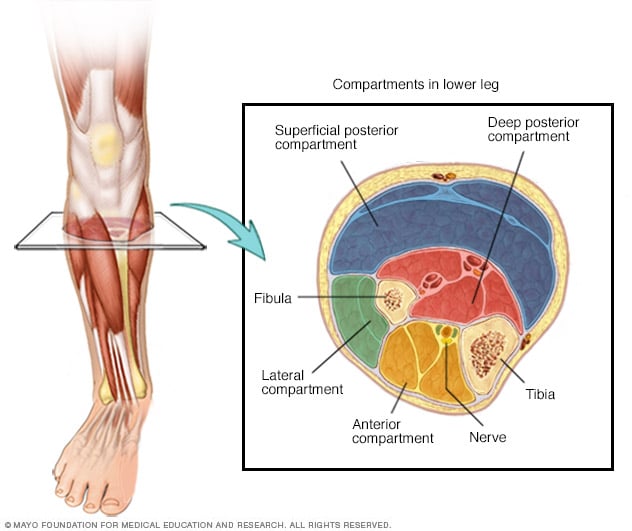

Chronic exertional compartment syndrome is a musculoskeletal condition brought on by exercise It can affect muscle compartments in any of your limbs but occurs most commonly in the lower legs The lower leg has four compartments and

Deep Posterior Compartment Syndrome Symptoms Causes Treatment

Compartment Syndrome Of The Lower Leg Physio Check

Compartment Syndrome Acute Chronic Anatomy And Operation

Compartment Syndrome Acute Chronic Anatomy And Operation